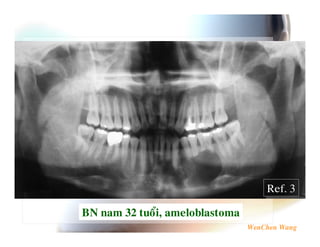

P$ # 4 $ 0 % 2 $ $ 5J K @ 2 E " L! &' $ ' MN O P 9 ( I F " * &0 0 " ;% ! 4 1 6 ! 4 7%& * Q Ref. 2 % 7 *" R 0('5 ! 0 '6 7 3 S 6. ' T 0 2 * F * *6 F Ref. 1

R4 7 # % $ >P$ # 4 K# $ ? $' 2 %& L! &' 2 MB 8 1 $ %0 ( ' 7%& ! 4 &' ( $U " %& L! &' P 9 & V *0 2 %& . 1%& ( 4 $ W 6 " 3 2! 5 ( &0 *5*; . 1& 1 6 4 " Ref. 3